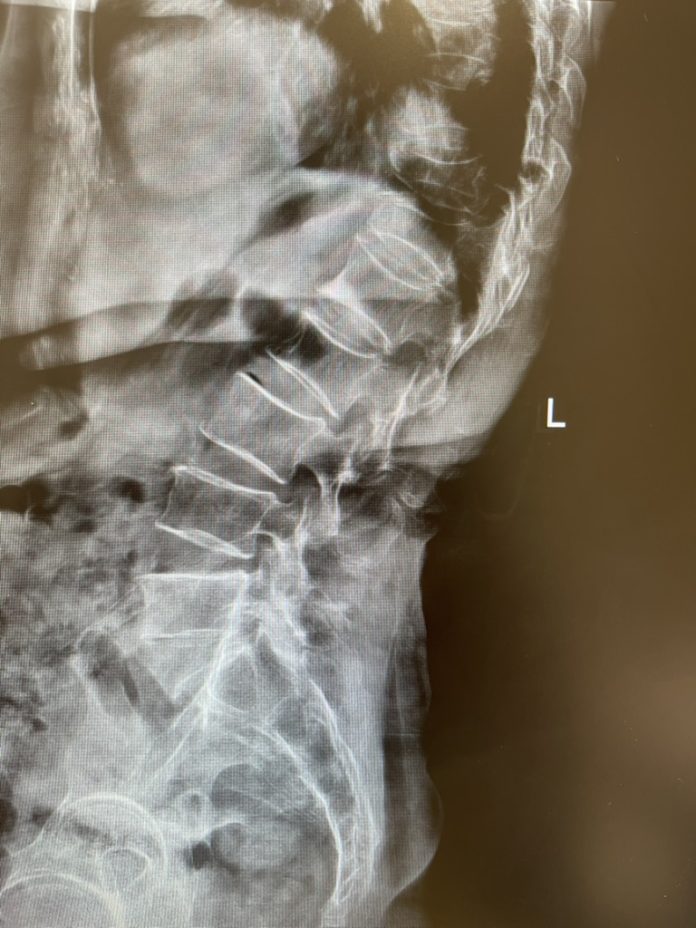

4. การตรวจมวลกระดูก (Bone Densitometry

– DXA): เป็นการใช้รังสีเอกซเรย์ระดับต่ำมาก สแกนดูที่

“กระดูกสันหลัง” และ “ข้อสะโพก”

ซึ่งเป็นจุดที่อันตรายที่สุดถ้าหัก ใช้เวลาเพียง 10-15 นาที ไม่เจ็บเลยครับ

หลังเริ่มค่อมหรือโก่ง

เกิดจากกระดูกสันหลังเริ่มยุบตัวลงทีละน้อย